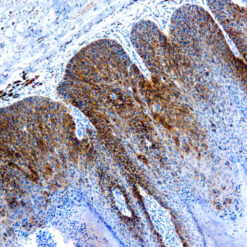

Synaptophysin (SYP02)

This antibody isspecific to a 38 kDa protein. Synaptophysin is an glycoprotein occurring in presynaptic vesicles of neurons in the brain, spinal cord, retina, vesicles of adrenal medulla and in neuromuscular junctions. This antibody reacts with neuroendocrine neoplasms of neural as well as epithelial types.

| Cellular Localization | Cytoplasmic |

| Positive Control Tissue | Pancreas |